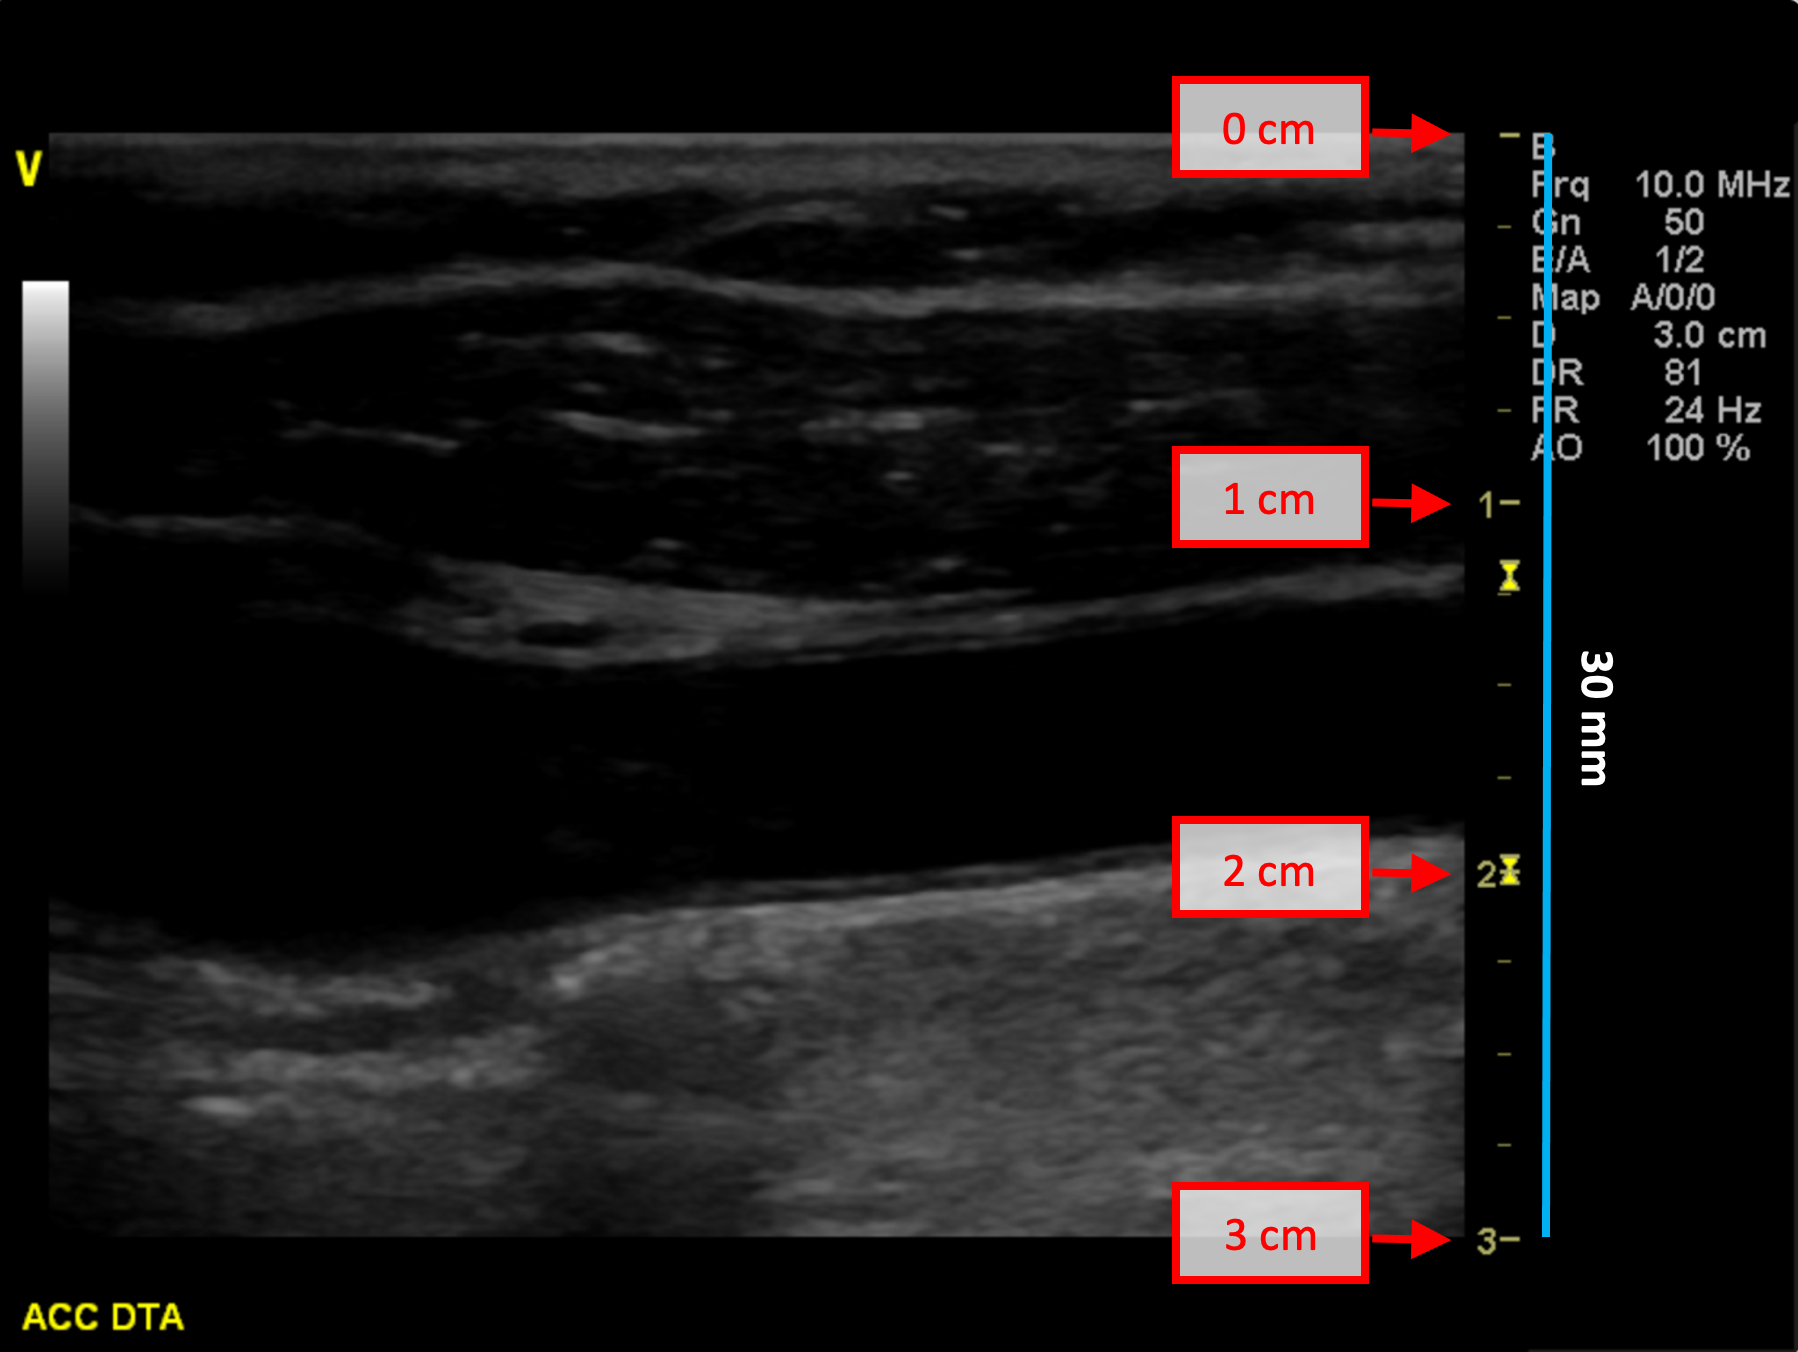

• Individuare, nell'immagine ecografica, una distanza nota (30 mm. nell'esempio in figura).

Esempi di calibrazione in modalità B

Le immagini seguenti mostrano esempi di calibrazione dell'immagine in modalità B. Gli elementi grafici in rosso indicano dove è possibile trovare informazioni sulla profondità dell'immagine nell'immagine ecografica.